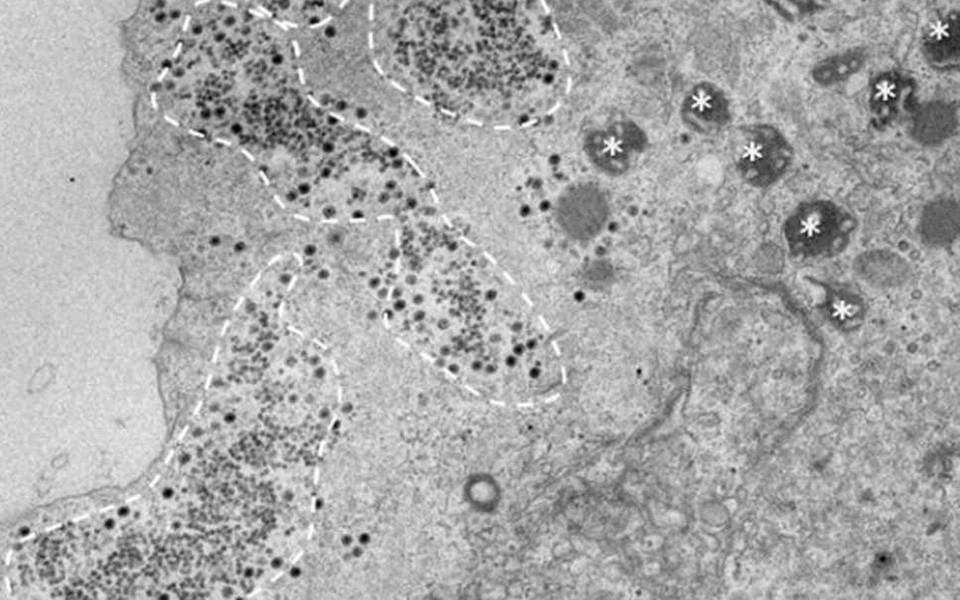

Ο νέος ιός ήταν σημαντικά μικρότερος από τους ιούς που συνήθως μολύνουν τις αμοιβάδες.

Όταν οι επιστήμονες προσπάθησαν να αποκωδικοποιήσουν το DNA του, διαπίστωσαν πάνω από το 90% των γονιδίων του δεν είχαν βρεθεί σε καμία προηγούμενη έρευνα.

«Ανακοινώνουμε την ανακάλυψη του Yaravirus, μιας νέας γενιάς ιού αμοιβάδας με μια αινιγματική προέλευση» δήλωσαν οι βιολόγοι που εξέτασαν τον ιό, στην επιστημονική ιστοσελίδα bioRxiv.